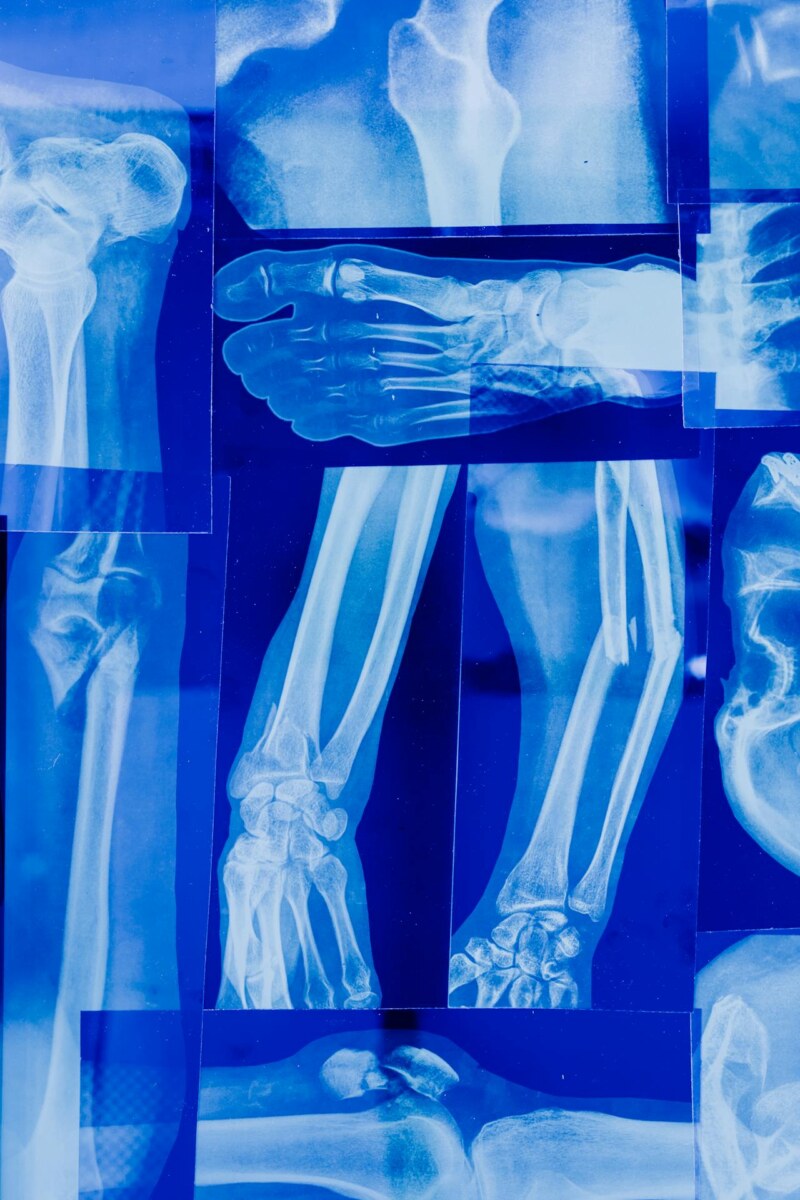

Για τους ενήλικες τα κατάγματα αποτελούν μία από τις κύριες αιτίες νοσηρότητας και θνησιμότητας. Υπάρχουν πολλοί παράγοντες κινδύνου μεταξύ των οποίων η ηλικία, το φύλο, η εμμηνόπαυση, το κάπνισμα, η υπερβολική κατανάλωση αλκοόλ και η έλλειψη σωματικής άσκησης. Παρόλο που τα ηλικιωμένα άτομα παραμένουν τα πιο επιρρεπή σε κατάγματα λόγω διαταραχών όπως μυϊκή αδυναμία και μειωμένη ισορροπία, νέες έρευνες επιβεβαιώνουν ότι επικίνδυνος για τη μυοσκελετική υγεία είναι ο χαμηλός Δείκτης Μάζας Σώματος, ίσως περισσότερο από την παχυσαρκία επισημαίνει ο Διδάκτωρ του Πανεπιστημίου Αθηνών και εξειδικευμένος στις αρθροπλαστικές ισχίου & γόνατος Ορθοπαιδικός Χειρουργός δρ Αθανάσιος Τσουτσάνης.

Οι περισσότερες μελέτες ασχολούνται με τις επιπτώσεις της παχυσαρκίας στην υγεία των οστών και την πιθανότητα κατάγματος από οποιαδήποτε αιτία. Αν και πολλοί πιστεύουν ότι τα παραπανίσια κιλά προστατεύουν, στην πραγματικότητα όσοι έχουν υψηλό Δείκτη Μάζας Σώματος αντιμετωπίζουν μεγαλύτερο κίνδυνο πτώσεων και συνεπώς καταγμάτων, κυρίως στον αστράγαλο και στα άνω άκρα, από εκείνους που έχουν φυσιολογικό βάρος.

Για την αυξημένη πιθανότητα να υποστούν κάταγμα τα λιποβαρή άτομα σπανίως γίνεται λόγος. Μα και αυτά αντιμετωπίζουν εξίσου σοβαρό κίνδυνο. Ο χαμηλός Δείκτης Μάζας Σώματος μπορεί να οδηγήσει σε κακή μυοσκελετική υγεία, δηλαδή σε μειωμένη οστική πυκνότητα, απώλεια μαλακών ιστών και μυϊκή αδυναμία και να αυξήσει έτσι τον κίνδυνο καταγμάτων.

Τα άτομα με χαμηλό σωματικό βάρος είναι πιο ευάλωτα σε κατάγματα και λόγω ελλιπούς απορρόφησης των κραδασμών, αλλά και της μείωσης της μηχανικής απαίτησης για μεταφορά του σωματικού βάρους, η οποία μπορεί να επηρεάσει την πυκνότητα των οστών.

Με ποια κατάγματα σχετίζεται η απώλεια βάρους

Η απώλεια βάρους φαίνεται ότι έχει στενή σχέση με τα κατάγματα στα άνω και κάτω άκρα όπως και στον κορμό. Ο κίνδυνος κατάγματος ισχίου είναι υψηλότερος σε εκείνους με φυσιολογικό βάρος που χάνουν βάρος, ακολουθούμενος από τα άτομα που δεν έχουν διακυμάνσεις στο βάρος τους, αλλά είναι σταθερά λιποβαρείς.